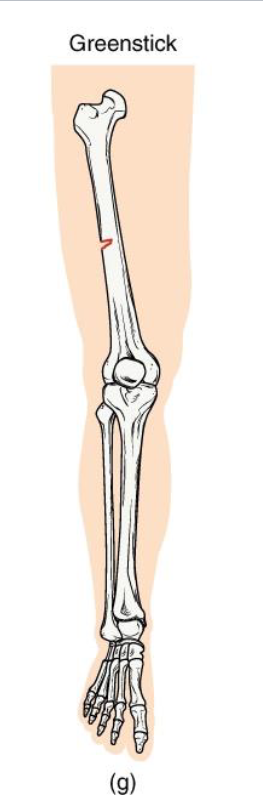

Greenstick Fracture

Definition: Incomplete break - bone bends and cracks on one side

Mechanism: common in children (softer, more flexible bone)

Clinical note: Often associated with forearm fractures in pediatrics.

Key concept: compare to bending a green twig - it splinters but doesnt snap

<p><strong>Definition: Incomplete break </strong>- bone bends and cracks on one side</p><p><strong>Mechanism</strong>: common in children (softer, more flexible bone)</p><p><strong>Clinical note: Often associated with forearm fractures in pediatrics.</strong></p><p><strong>Key concept</strong>: compare to bending a green twig - it splinters but doesnt snap</p>